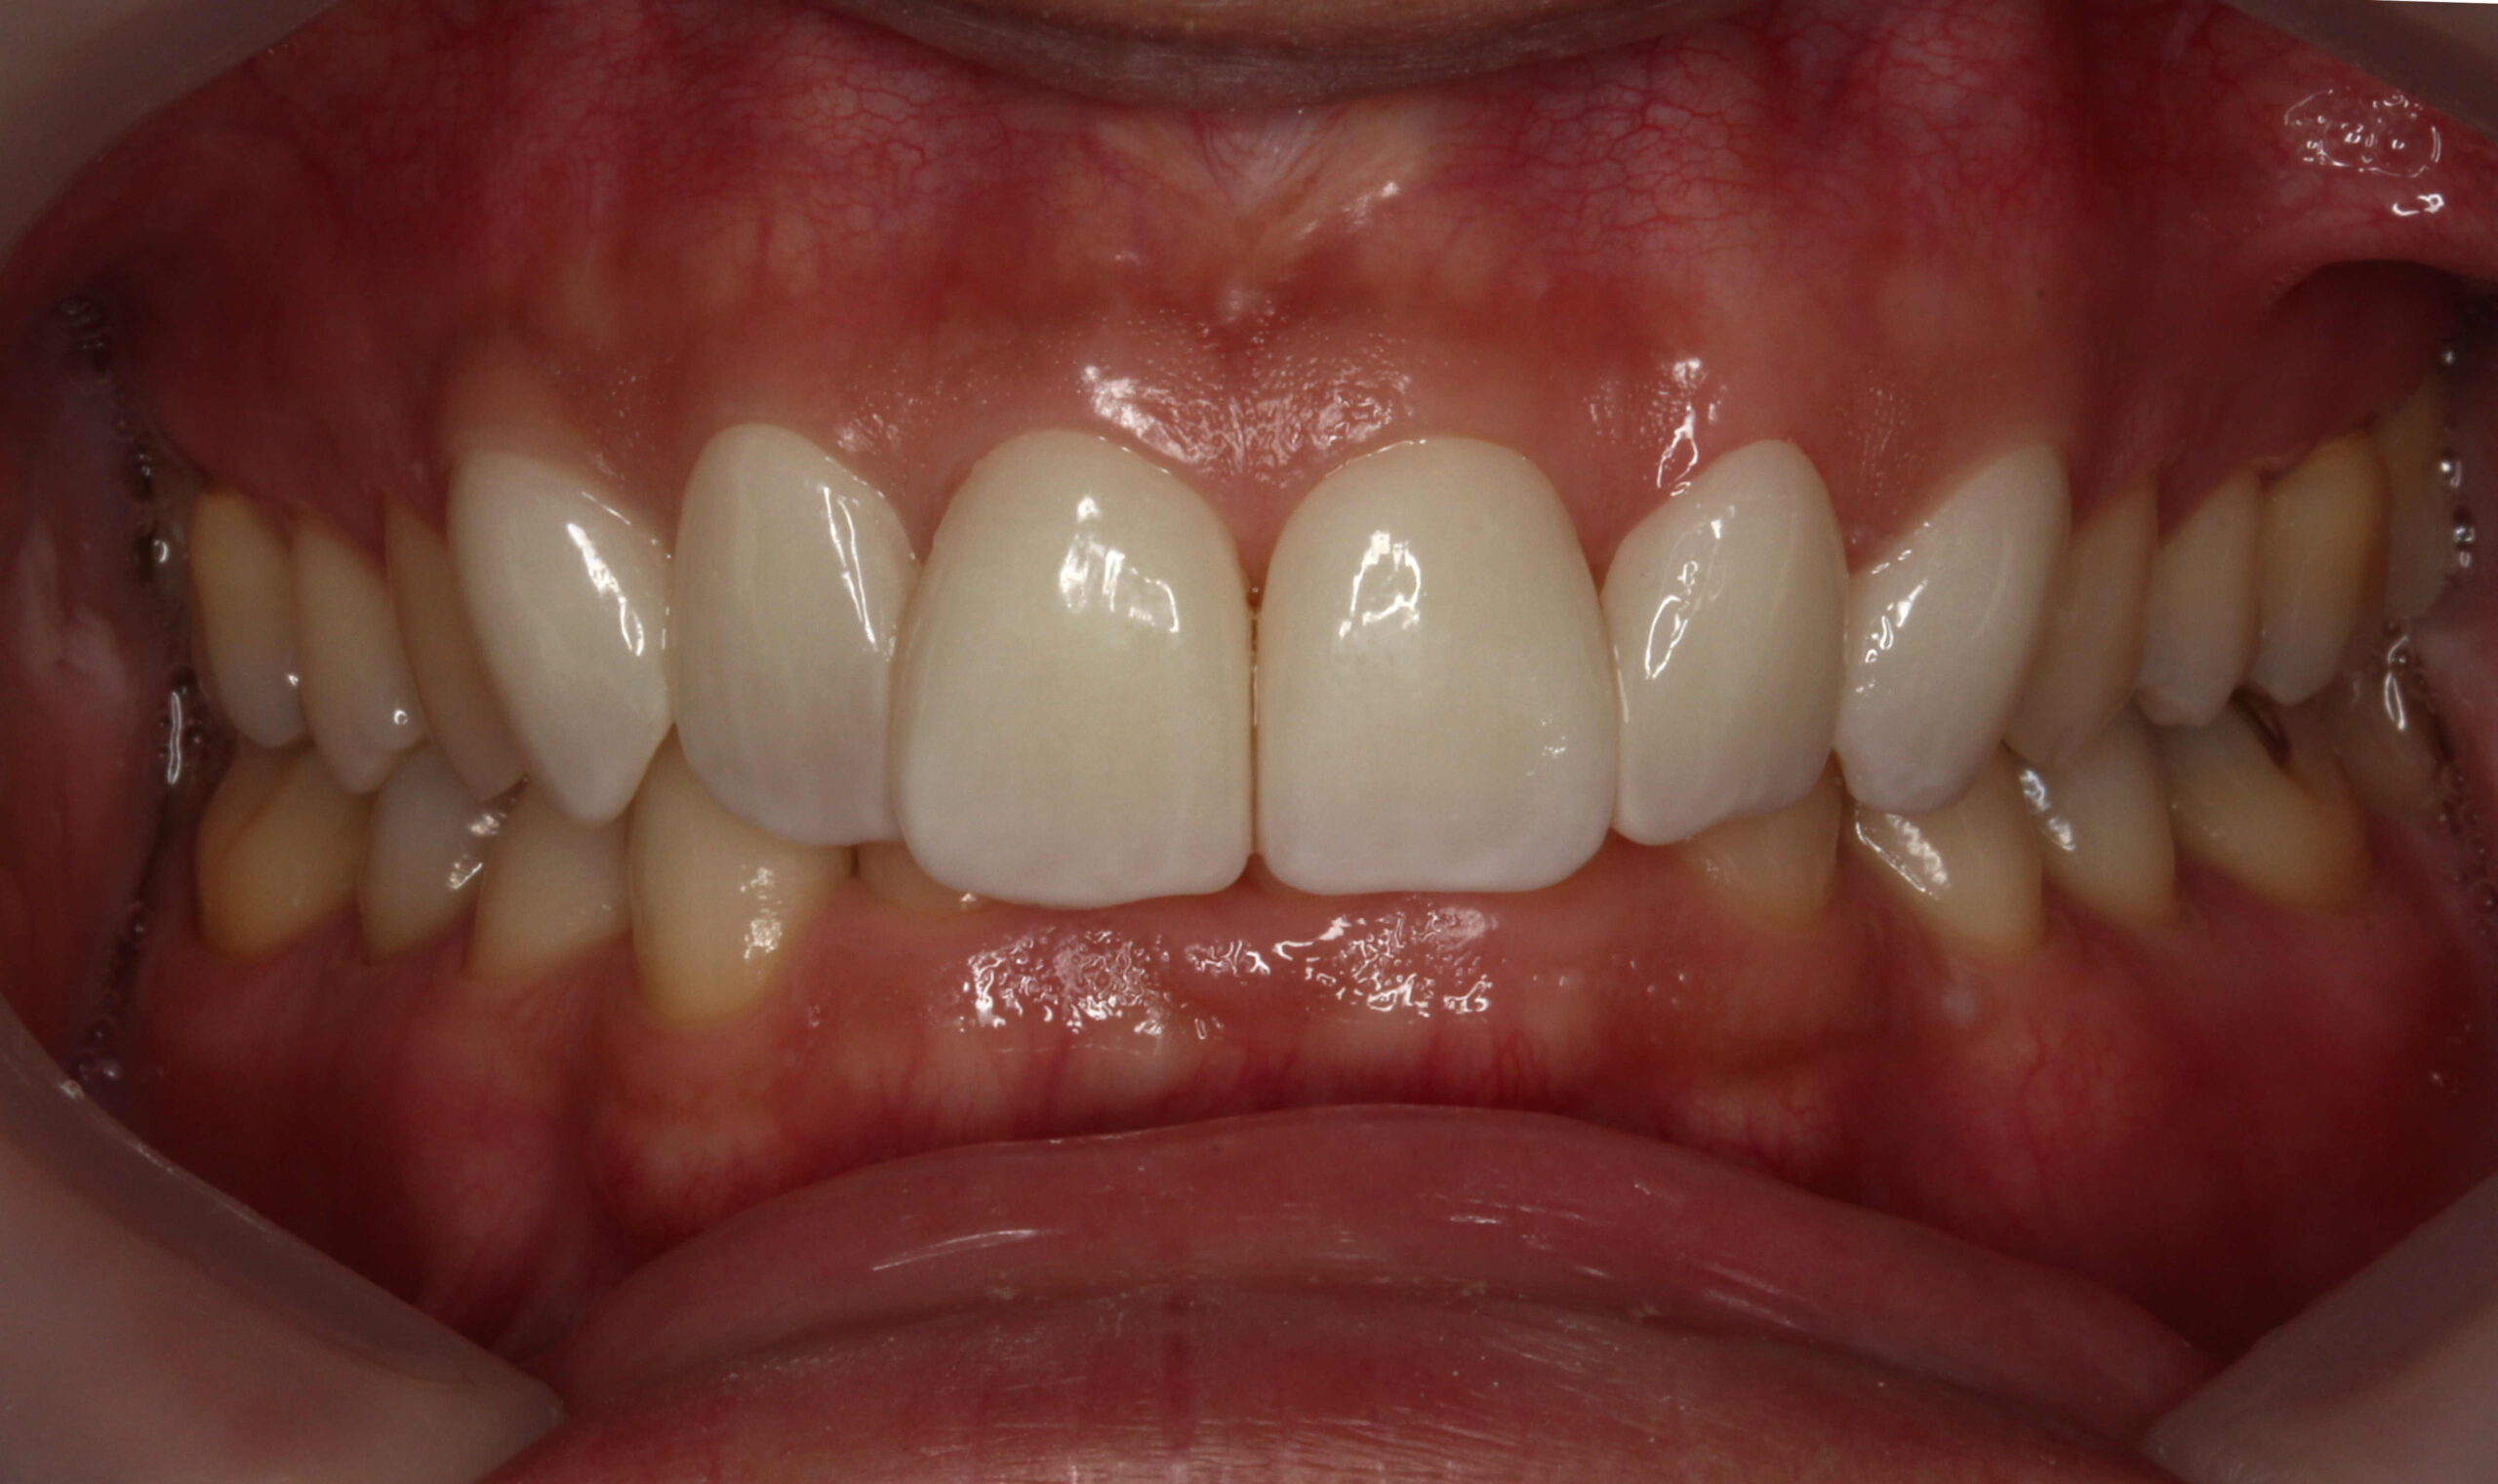

前歯4本の削らないラミネートベニア症例です。

前歯の歯並びと色味が気になっていた方です。

とにかく自然に、少しだけキレイに治したいとのことでした。

削らないラミネートベニア4本を周りの歯と調和させ、自然な色味で合わせました。

とてもとても喜んで頂けました。(削らないラミネートベニアは通常では6本や8本で行うことが多いです。)

この症例も天然歯は削らない審美歯科です。